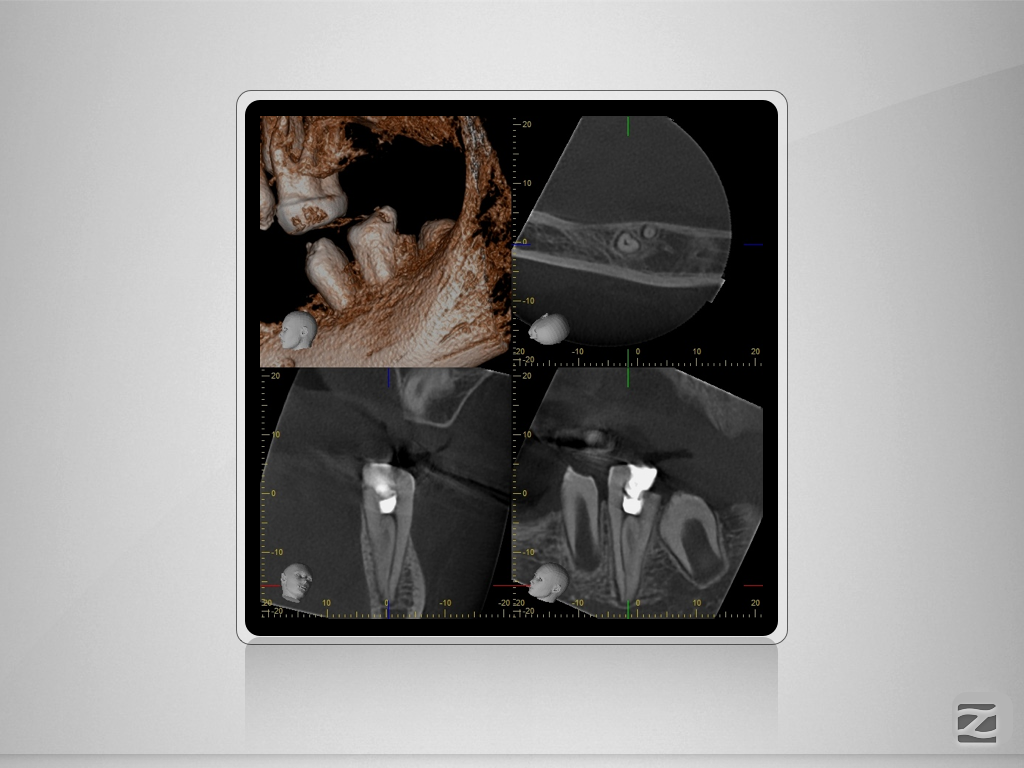

36D.006

1024 × 768

Doppeltes C